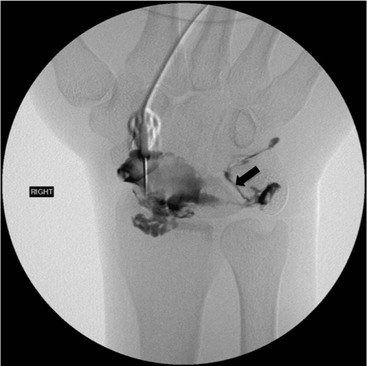

Abnormal communication between the radiocarpal and midcarpal joints may be seen on arthrography (Fig. 46-28), which is usually combined with MRI or CT16 (Figs. 46-29 and 46-30). However, direct visualisation of the ligaments is possible with conventional MRI. The most important features to describe that help determine management include the following: